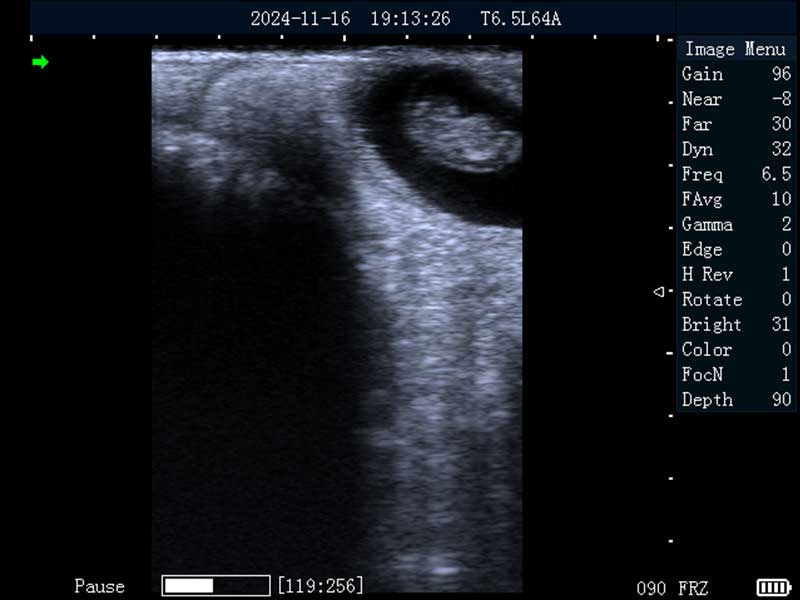

牛妊娠40日龄